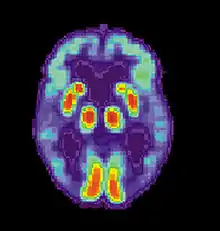

T. Awipi and L. Davachi sought to provide evidence of competing subregions in the medial temporal lobe (MTL) that differed on the type of content they encoded. The researchers conducted a study in which subjects were asked to perform an encoding task in a functional magnetic resonance imaging (FMRI) scanner, where they were presented with 192 full colour photographs of scenes (containing a centrally presented novel scene and a smaller image of one of six objects). Participants were also instructed to imagine using the presented object in each scene, and were asked to report whether they were successful. A memory test was administered after participants were removed from the scanner. The test consisted of all previously viewed scenes (old) and an equal number of novel scenes (new). They were asked to make an old/new judgement, and if the scene was responded as being old, they were asked to report it as being "remembered" or "familiar". They were then asked to pick an object that was paired with that scene. The researchers were trying to determine the levels of activation for source recollection for the objects paired with the scene during encoding.[19]

The researchers found that perirhinal cortex activation was greater for objects recalled, and parahippocampal cortex activation was greater when scenes were recalled.[19] The results provide evidence of distinct encoding activation in the subregions of the medial temporal lobe.[19] The first subregion is the perirhinal cortex, which encodes item information. The second subregion, the parahippocampal cortex, is involved in source information. The evidence provides support for the role of the right perirhinal cortex in attributing an object to the right source.[19] As decreased activation was associated with poorer performance, decreased activation of the right perirhinal cortex could be a possible mechanism for source confusion.